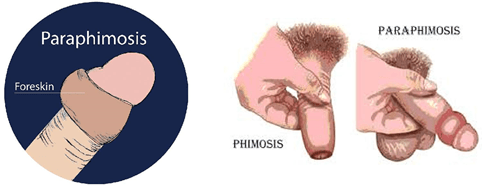

Paraphimosis:

Paraphimosis is a condition in which the foreskin is left retracted because of entrapment of the tight prepuce proximal to the corona,ie: the round elevated part.

The glans engorges and the prepuce becomes edematous because of lymphatic and venous congestion. Thiscould happen because boys have been encouraged to retract the foreskin for physiological phimosis by parents or medical staff. In most instances,manual compression can reduce the preputial edema within the first few hours. In difficult cases, various techniques are described, including applying granulated sugar to the penis, adding multiple punctures to the edematous foreskin before compression, injecting hyaluronidase beneath the narrow band to release it, and wrapping the distal penis in a saline solution–soaked gauze swab and squeezing gently but firmly for 5–10 min. Thereafter, physicians are supposed to push forcefully on the glans with the thumbs, while pulling the foreskin with the fingers. However, an emergency dorsal slit may be necessary in late cases. Some authors advise circumcision for paraphimosis because of its tendency to recur,whereas others insist that circumcision is not mandatory because the foreskin will continue to develop normally.